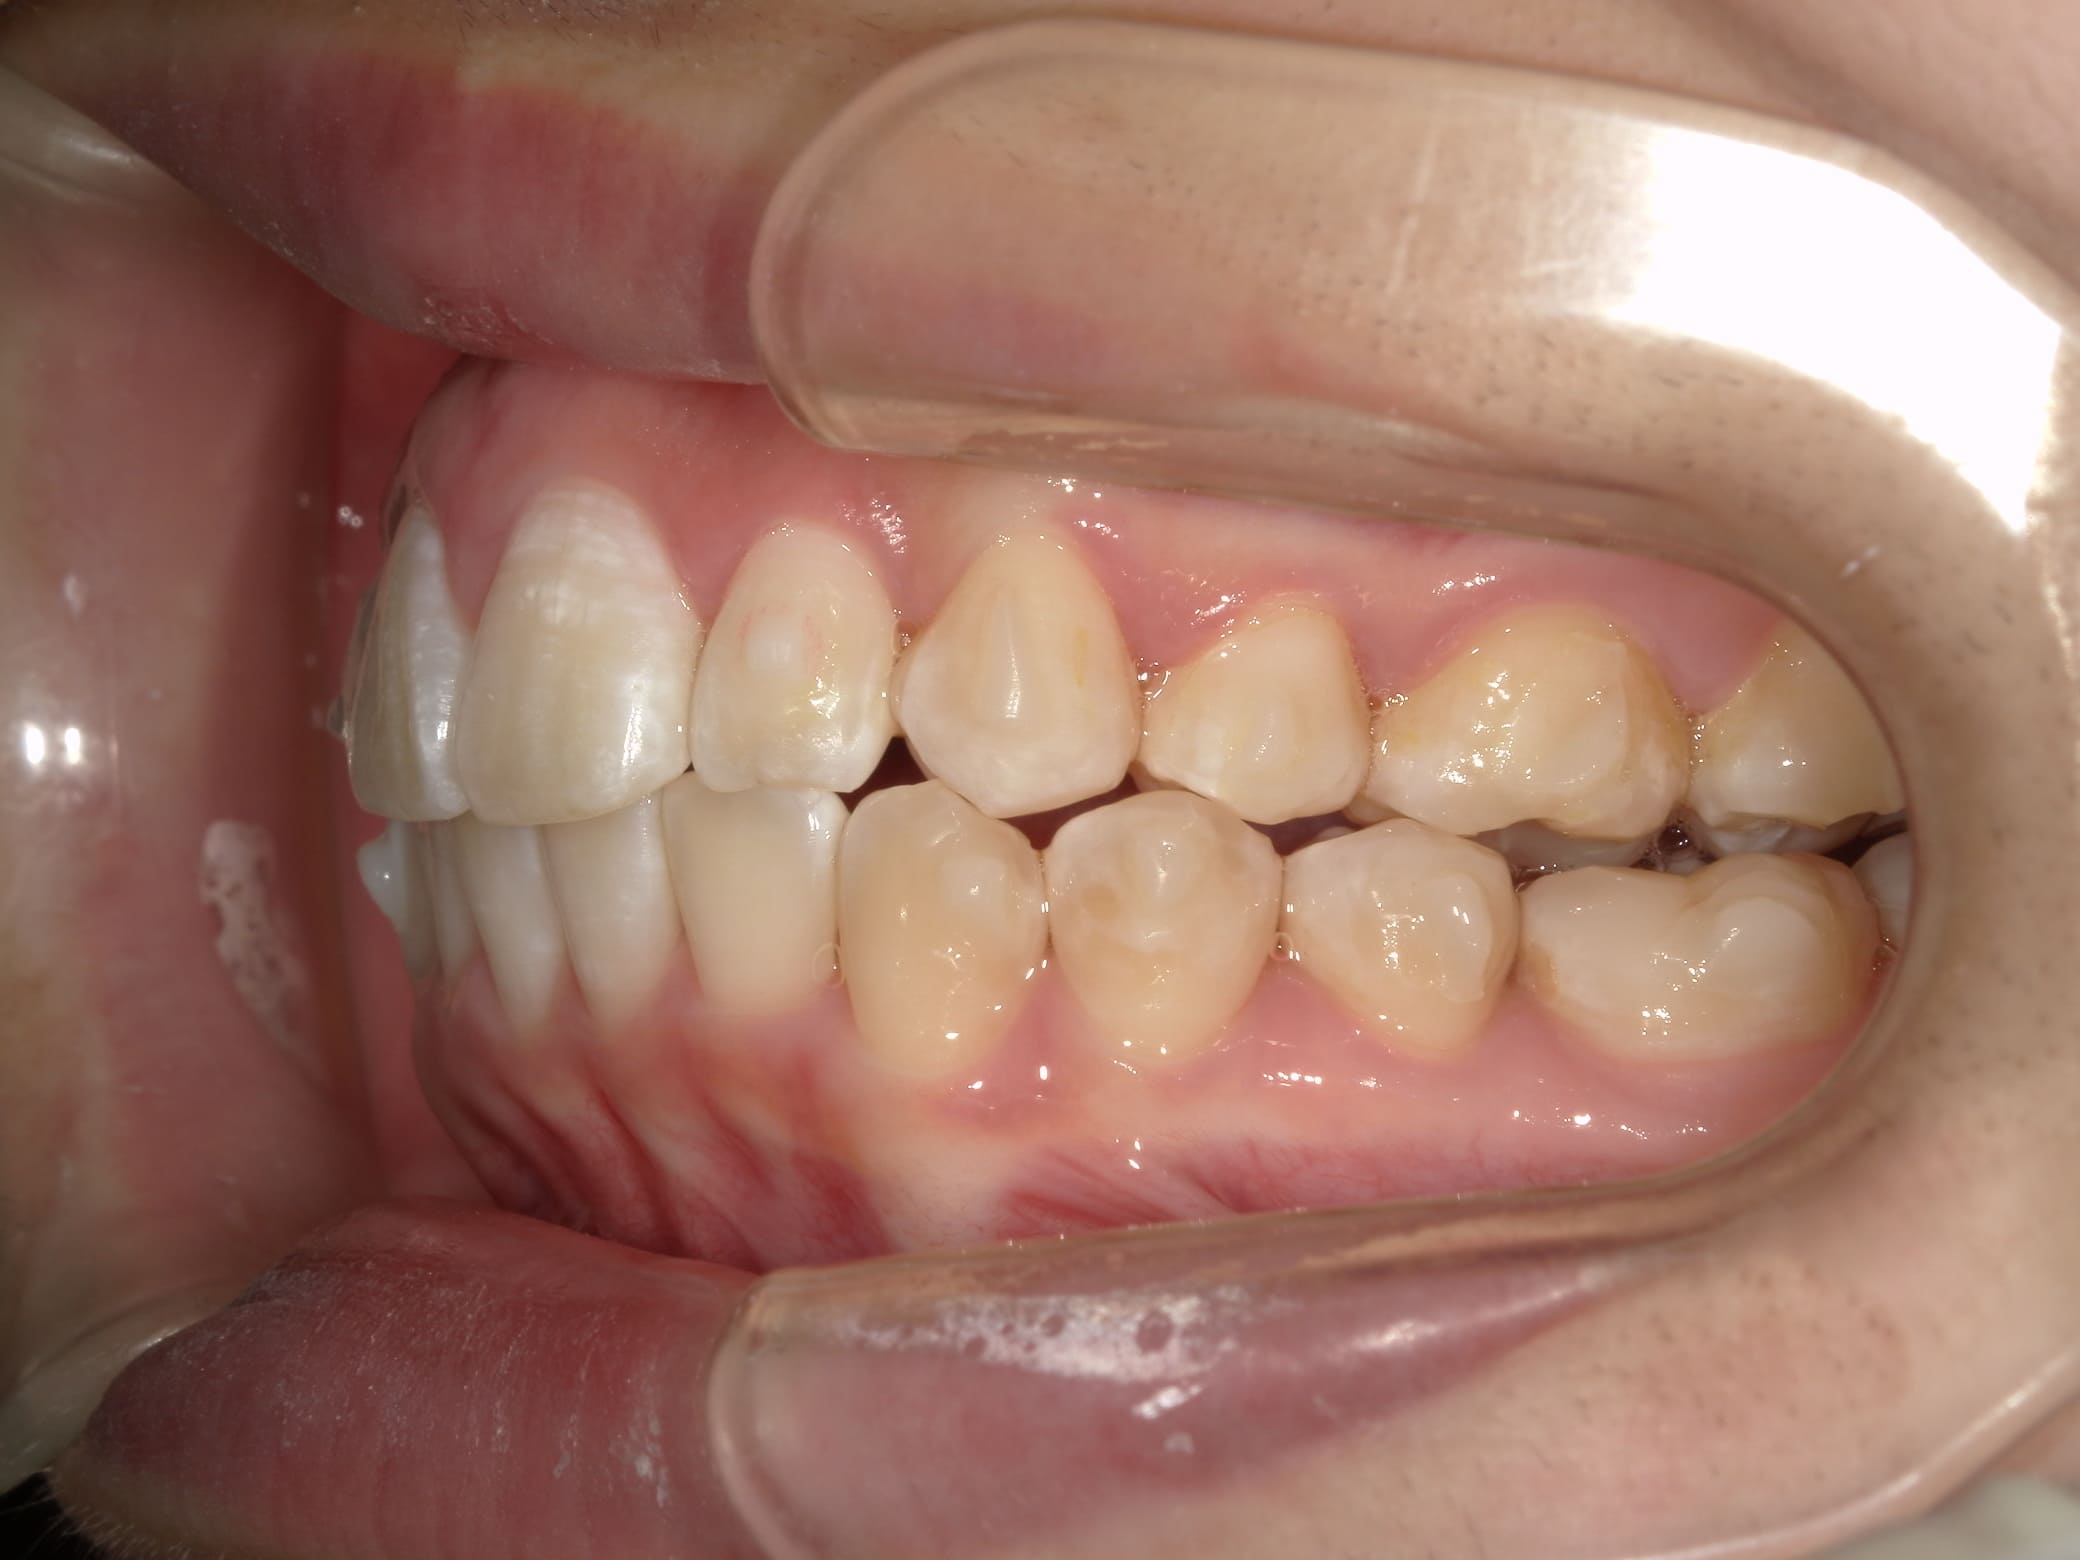

| 年齢・性別 | 21歳 |

|---|---|

| 主訴 | 叢生が気になる・前歯に埋伏歯がある |

| 治療期間・回数 | 6ヶ月 |

| 費用 | 935,000円 |

| 上顎の左側3番が埋伏していたため、上顎左右の3番および親知らずを抜歯し、矯正治療を行いました。 治療開始からおよそ6ヶ月で歯列が整い、審美的にも機能的にも良好な結果が得られた症例です。 |